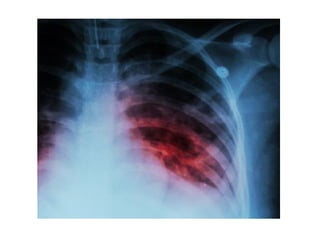

Lung abscess

• Lung abscess is defined as necrosis of the

pulmonary tissue and formation of cavities

containing necrotic debris or fluid caused by

microbial infection. The formation of multiple

small (< 2 cm) abscesses is occasionally

referred to as necrotizing pneumonia or lung

gangrene.